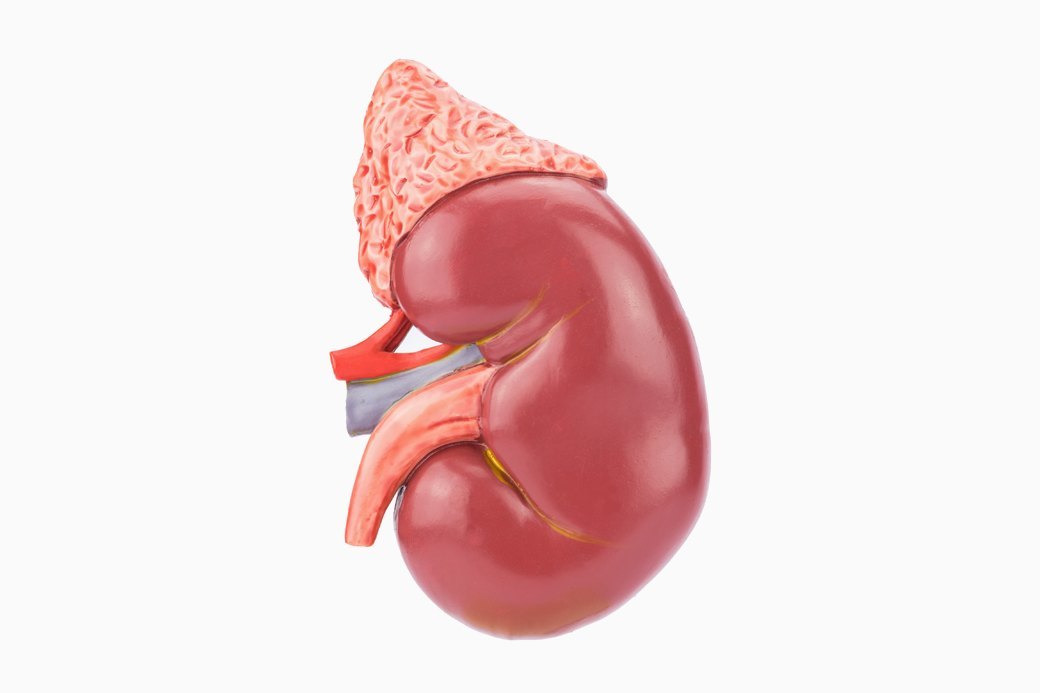

Єдина дозволена форма — добровільне донорство без винагороди. Живий донор (родич чи інша особа з сумісністю) може віддати нирку безкоштовно, отримуючи лише компенсацію витрат на обстеження, проїзд і втрачений заробіток. Держава покриває операцію повністю — близько 800 тисяч гривень за нирку через НСЗУ.

Ризики для здоров’я та життя донора

Видалення нирки — серйозна операція. Навіть у найкращих клініках існує ризик ускладнень: кровотечі, інфекції, проблеми з серцем під час наркозу. Після операції одна нирка бере на себе всю роботу, тому життя змінюється назавжди.

Без належного післяопераційного догляду (якого на чорному ринку майже не буває) розвивається хронічна ниркова недостатність, гіпертонія, серцево-судинні захворювання. Дослідження показують, що донори на чорному ринку мають у рази вищий ризик смертності в перші роки після операції порівняно з легальними донорами.

Багато хто втрачає працездатність: важка фізична праця стає неможливою, спорт обмежується, потрібен постійний контроль аналізів. А якщо друга нирка постраждає — людина опиняється на діалізі або в черзі на трансплантацію, як і ті, кому вона “продала” орган.

Живе донорство можливе для близьких родичів чи тих, хто має емоційний зв’язок. Процес: обстеження, психологічна оцінка, операція в одному з 26 сертифікованих центрів (Київ, Львів, Запоріжжя тощо). У 2025 році провели понад 650 органних трансплантацій, з них багато нирок.